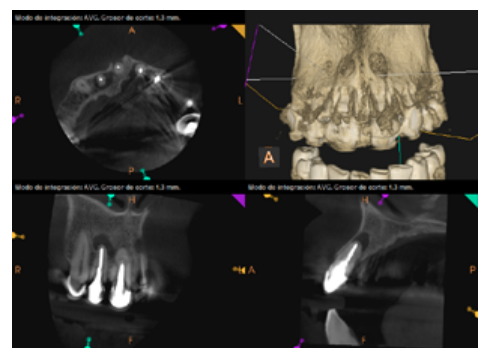

To confirm the endodontic origin and the size of the lesions, tomographic examinations were performed with a slice thickness of 75 microns using CBCT CS8100 (Carestream Dental™), in which radiolucent periapical lesions were observed at the level of 12, 11, 21 (with bicortical involvement), 25 and vestibular roots at 26 (Figures 4 to 8).

Six months later, the patient went for a check-up without any symptoms, both anteriorly and posteriorly. Periapical radiographs showed a decrease in the size of the pre-existing radiolucent periapical lesions (Figures 10 and 11). Given that the lesion on 25 remained to be treated, a control CBCT was performed where improvement at the level of 26 was verified (Figure 12), so microsurgery on 25 was scheduled.

After the microsurgery was performed on 25, the patient had no symptoms and the control tomographies at 12 months (in 25) and at 18 months in the remaining teeth showed regeneration of pre-existing radiolucent periapical lesions on all treated teeth (Figures 13 to 16).

Radiological checks were carried out at 6, 12 and 18 months using CBCT, which showed the absence of symptoms and a reversal of the chronic infection, as well as progressivity and stability in apical bone regeneration. At the level of 21, periapical radiopacity was observed, without loss of volume, and an absence of invasion of the space preserved by the surrounding soft tissue. Although some authors have used plasma rich in growth factors (PRGF) associated with Bio-Oss™ and Bio-Gide™ in cases similar to ours, we obtained adequate results without using PRGF as an additional technique13.